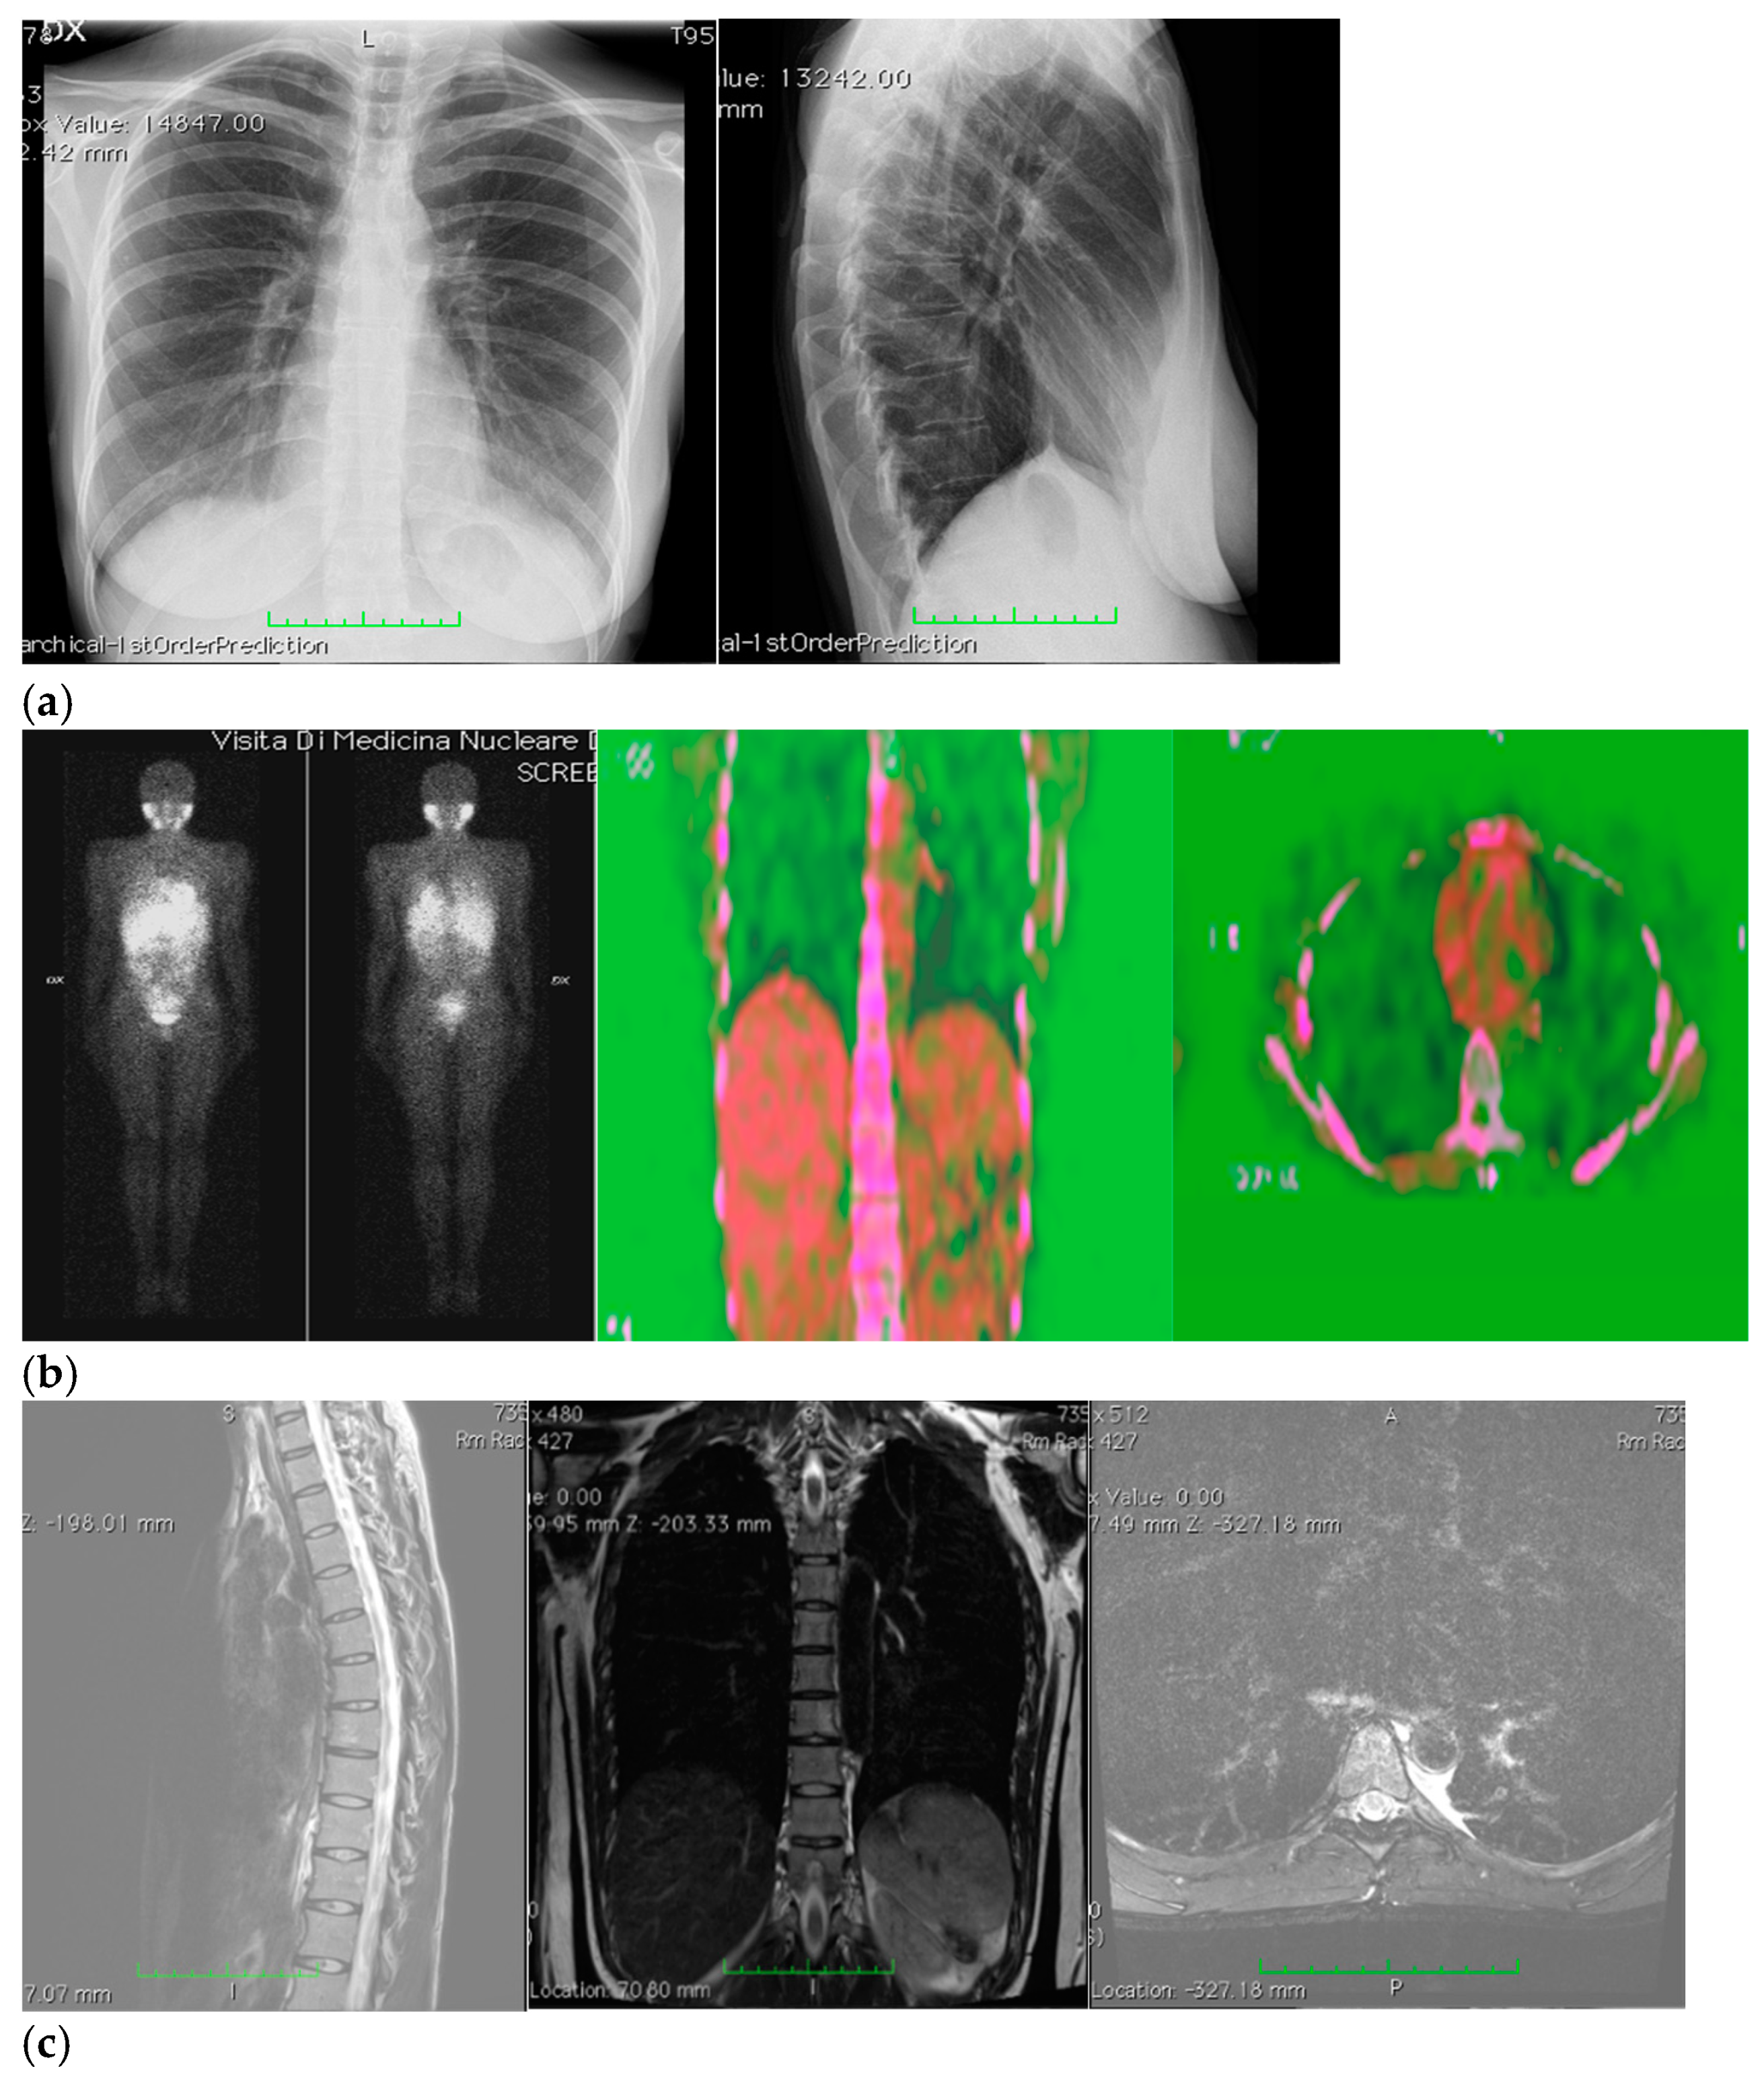

Therefore, her GP prescribed a chest X-ray, which revealed a voluminous opacity in her posterior mediastinum on the left (Figure 1a); subsequently, the GP referred the patient to a thoracic surgeon, who prescribed a series of imaging (Figure 1b–h) tests to biologically circumscribe the lesion, in order to evaluate its metabolic activity and its eventual malignancy. After these further investigations, the patient’s histopathological diagnosis was of poorly differentiated neuroblastoma ALK + (IIC), I stadium [,]. The patient was inserted in the operating room schedule for surgical excision.

Figure 1.

(a–h) Imaging assessments for pre-surgical evaluation. (a) X-ray scans. (NOTE: Voluminous opacity in the posterior mediastinum on the left, with a major axis of about 12 cm). (b) Thorax CT scan with Iodixanol. (NOTE: Solid, oval-shaped tumour in the left posterior mediastinum, measuring 8 × 5.5 cm. Anteriorly, the mass pressed the left main bronchus from behind, while medially it displaced the thoracic aorta—sitting directly on the metamers T5 to T8, and compressing the hemiazygos vein. The mass also went through the intervertebral foramen, between T6 and T7, and partially through the VI and VII intercostal spaces; laterally, it caused dystelectasis of the lung parenchyma. The NB had an irregular density, with innumerable small foci of calcification, and areas of slightly blurred impregnation of the contrast medium). (c) Tracheobronchoscopy. (NOTE: Left lower lobe bronchus with a luminal narrowing, resembling an extrinsic compression. In detail: left lower lobe bronchus, left main bronchus, trachea and carina). (d) Thorax MRI with Gadoteridol. (NOTE: Presence of a mass with maximum dimensions of approximately 7.5 × 5.5 cm axially and 10 cm of craniocaudal extension, limited by a plane passing from upper T6 to lower T9. Extension up to the ipsilateral lung, which caused a moderate compression and a slight compressive effect, also on the left sections of the heart (in particular the atrium). Slight anterior displacement of the ipsilateral pulmonary hilum structures; the neoplasm also came into contact with the aorta. The tumour went through the left T6–T7 intervertebral foramen—taking up space at the foraminal level, not at the level of the spinal canal—and it also extended up the corresponding intercostal space; it was compatible with a lesion originating from the nerve sheath arising from the T6–T7 foraminal region). (e) Total-Body PET/CT. (NOTE: Presence of an increased glucose metabolism lesion in the posterior mediastinal area, showing a necrotic portion and a metabolically more active portion, located in the medial side and infiltrating the posterior arch of the 6th left rib). (f) Thorax CT scan with Lopromide. (NOTE: Minor volumetric increase of the known space-occupying lesion, which maintained similar densitometric characteristics, clear limits, and maximum diameters equal to 8.5 × 6 cm on the transverse plane, with a maximum longitudinal extension of 11 cm. The solid component which went through the intercostal space between T6 and T7 was substantially unchanged. Absence of pleural or pericardial effusion). (g) Total-body scintigraphy with metaiodobenzylguanidine. (NOTE: The examination confirmed that the neoplasm was confined to the mediastinum only. The area of greater contrast medium enhancement corresponded to the left hemithorax, in particular, to the left posterior mediastinal region, from T6 to T9). (h) Thorax MRI with Gadoteridol. (NOTE: Slight increase in size of the known space-occupying lesion in the posterior mediastinum (85 × 60 × 103 mm vs. 80 × 55 × 100 mm). At T6–T7 level, the mass occupied some left foraminal canal space. Next to the known lesion, pleural effusion thin layer (maximum thickness of 11 mm)).